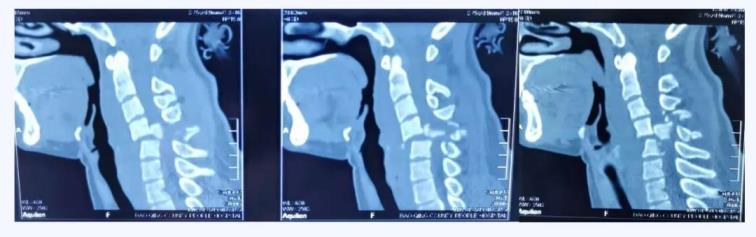

經(jīng)查,病人確診為“頸椎骨折脫位 、頸髓高位損傷四肢癱”,以致四肢感覺(jué)運(yùn)動(dòng)均喪失。第五頸椎椎體完全脫位于后方椎管內(nèi),頸脊髓損傷嚴(yán)重,這類(lèi)損傷導(dǎo)致脊髓水腫向上蔓延,可殃及呼吸循環(huán)控制中樞,患者隨時(shí)都有呼吸循環(huán)驟停危及生命的風(fēng)險(xiǎn)。我院骨科首席專(zhuān)家、業(yè)務(wù)院長(zhǎng)喬建民教授聞?dòng)嵹s到醫(yī)院進(jìn)行緊急救治。一般的頸椎骨折脫位,只需將脫位的椎體復(fù)位并固定即可,但該患者由于脫位的第5頸椎椎體完全脫位至椎管內(nèi),導(dǎo)致相應(yīng)節(jié)段頸脊髓受到嚴(yán)重?cái)D壓、損毀、變形,已無(wú)法手術(shù)將其復(fù)位,只能選擇切除。手術(shù)部位是高位頸脊髓神經(jīng),并緊鄰椎動(dòng)脈,稍有不慎就會(huì)加重?fù)p傷,危及生命。手術(shù)難度之高、風(fēng)險(xiǎn)之大,是可想而知的。要完成這臺(tái)如此高難度的手術(shù),不單單是對(duì)術(shù)者技術(shù)能力的考驗(yàn),更是對(duì)醫(yī)者心智和意志的挑戰(zhàn)。

術(shù)前CT